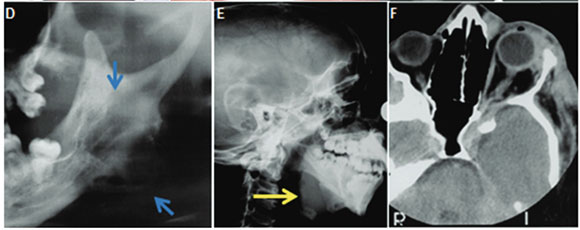

Cropped pantomograph showing sharply demarcated lytic lesions of left mandibular ramus and angle and an enlarged mandibular notch, red arrow (Figure C). Follow-up cropped pantomograph three years later showing subperiosteal "blister" lesion at left mandibular ramus, fusiform enlargement of the left mandibular canal, and "elongated" left condyle, blue arrows (Figure D). Lateral skull radiograph demonstrating neurofibroma subjacent to mandible which has resulted in upward displacement of lower border, yellow arrow (Figure E). Figure F is a coronal CT scan showing the soft tissue mass affecting the left orbit. A diagnosis of multiple neurofibromatosis was made. The classic description of this disease was given by von Recklinghausen in 1882 and the disease is often mentioned together with his name. The main features of the disease are the presence of multiple subcutaneous neurofibromas, and café au lait cutaneous pigmentation. Neurofibromatosis occurs in all races and is found in about 1 in 3,000 in the general population. Affected patients develop multiple neurofibromas. Superficial lesions are sessile or pedunculated, frequently consisting of numerous smooth-surfaced nodules that are widely distributed in the skin. Deeper, more diffuse lesions, or "elephantiasis neuromatosa" are often large in dimension. Moreover, most affected individuals have asymmetric areas of alanine pigmentation of the skin, termed café au lait spots. Intraoral neurofibromas occur in up to 20% of cases. When neurofibromas are present within the jaws, they are usually associated with the mandibular nerve, resulting in a fusiform enlargement of the canal with pain or paraesthesia. In the early literature, malignant transformation of neurofibromas was reported to occur in 15% of patients. Radiolucent defects involving the maxilla and mandible have been described in some cases. Generally the radiolucent areas are closely related to the foramina of the trigeminal nerve. The cardinal radiologic features are: fusiform enlargement of mandibular canal, sharply defined, and occasionally corticated radiolucency, subperiosteal "blister" lesion and enlargement of the jaw adjacent to a soft tissue tumour.